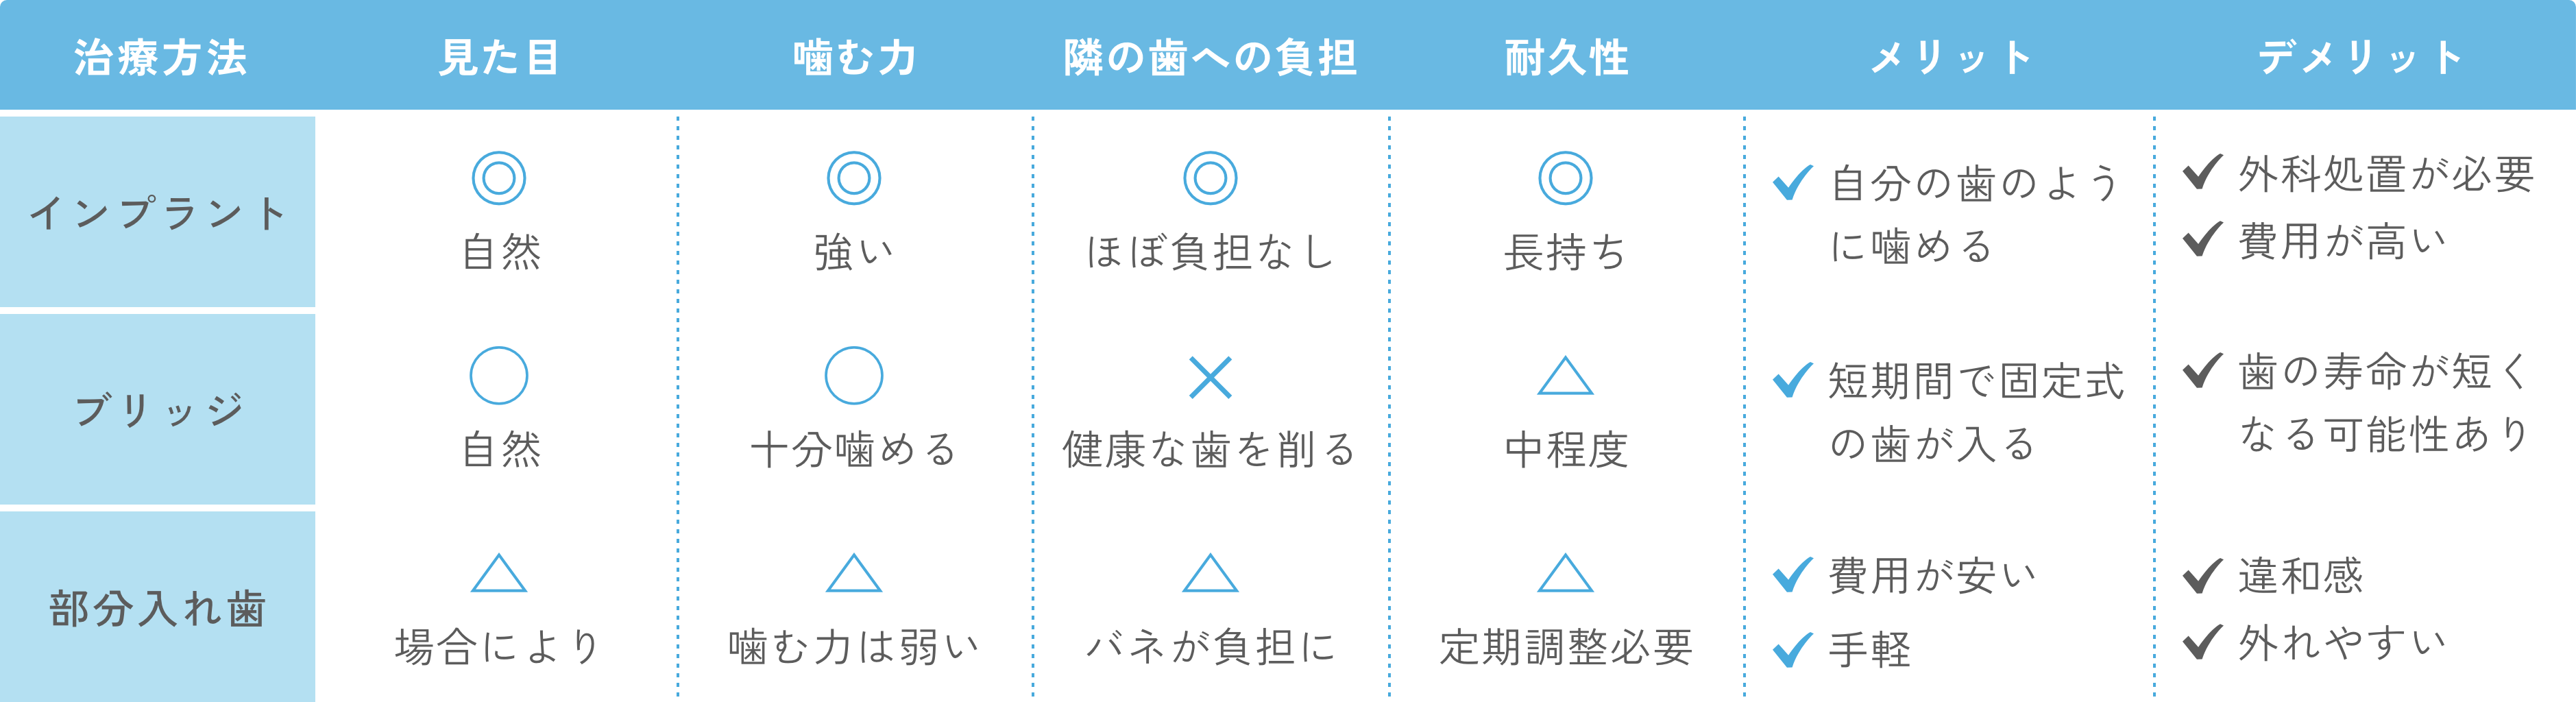

歯を失うと、「噛みにくい」「見た目が気になる」「隣の歯に負担がかかる」など、さまざまな問題が生じます。インプラント治療は、失った歯の機能や見た目を自然に回復させる治療で、自分の歯のような噛みごこちが得られることが最大の特徴です。

インプラントは、歯を失った部分の顎の骨に「チタン製の人工歯根」を埋め込み、その上に人工歯(セラミックの歯)を装着して歯の機能を回復する治療です。